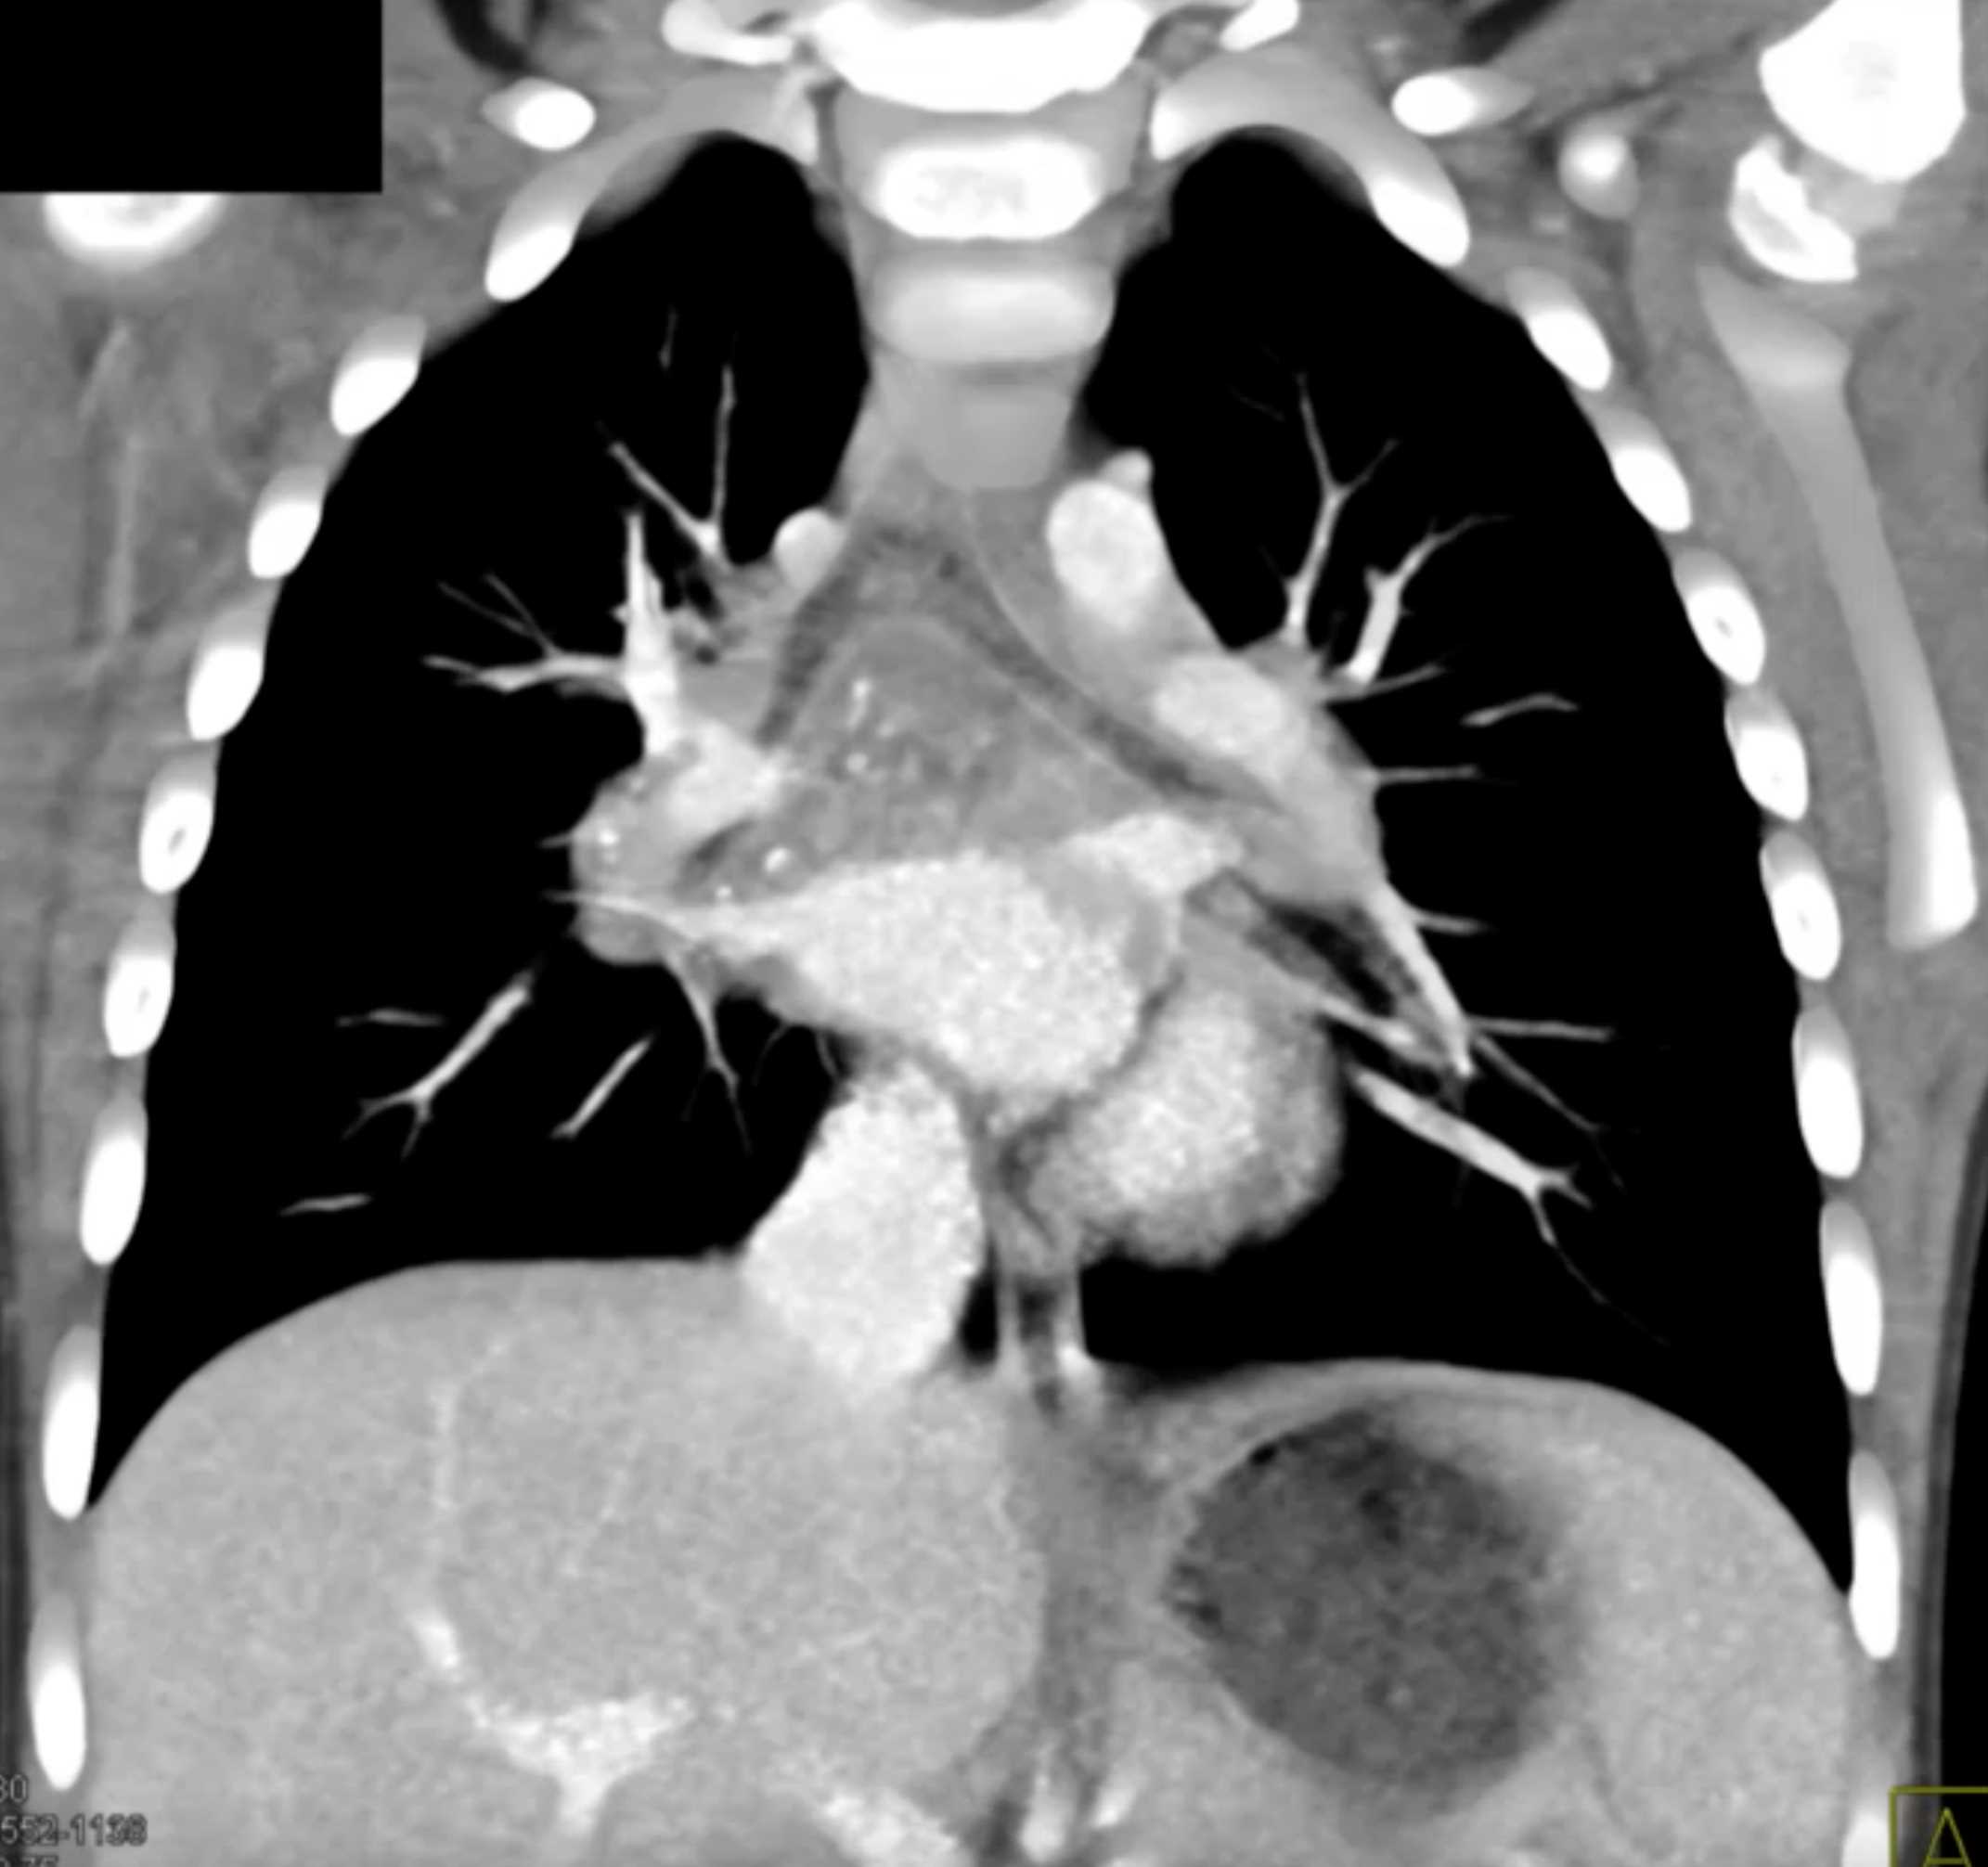

Histoplasmosis and Normal Thymus